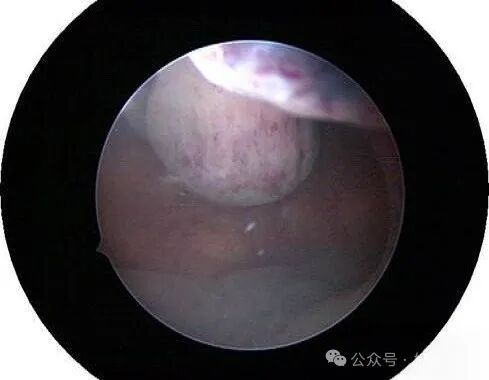

囊胚,100个细胞左右,形成液腔(受精后第4日)。受精后5~6日,囊胚的透明带消失。

宫腔后壁孕囊

宫腔前壁孕囊

宫腔镜下的胚胎图解